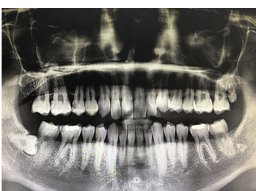

사랑니 발치 과정 주의사항에 대해 알아보려고 합니다. 사랑니는 대부분 어린 시절에 발생하는 치아로, 일반적으로 18~25세 사이에 생기는 3번째 대구치를 말합니다. 일반적으로는 상아질로 된 다른 이빨과 마찬가지로 식이기구의 일환으로 사용되지만, 때로는 주변 치아와 충돌하여 통증이나 발치가 필요한 경우도 있습니다.사랑니는 일반적으로 적절한 공간이 없어서 자리를 잡지 못하고 다른 이빨과 충돌할 가능성이 높습니다. 이러한 충돌은 주변 치아의 이상을 유발할 수 있으며, 치아의 교정이 필요할 수도 있습니다.

사랑니 발치는 일반적으로 부분 마취 후 수술실에서 이루어집니다. 수술 전에는 환자의 건강 상태와 치아의 위치와 상태를 파악하기 위해 치과 전문의가 진단을 하게 됩니다.